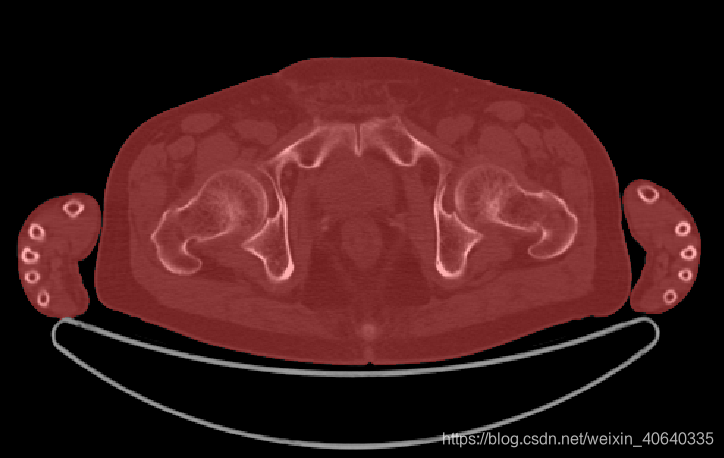

机床MASK示例:

红色部分就是机床mask了,结果还不错,再配合最开始的方法,获得人体的mask